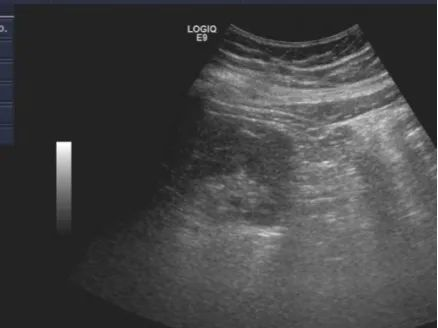

腹腔镜下肾穿刺后肾周无明显血肿